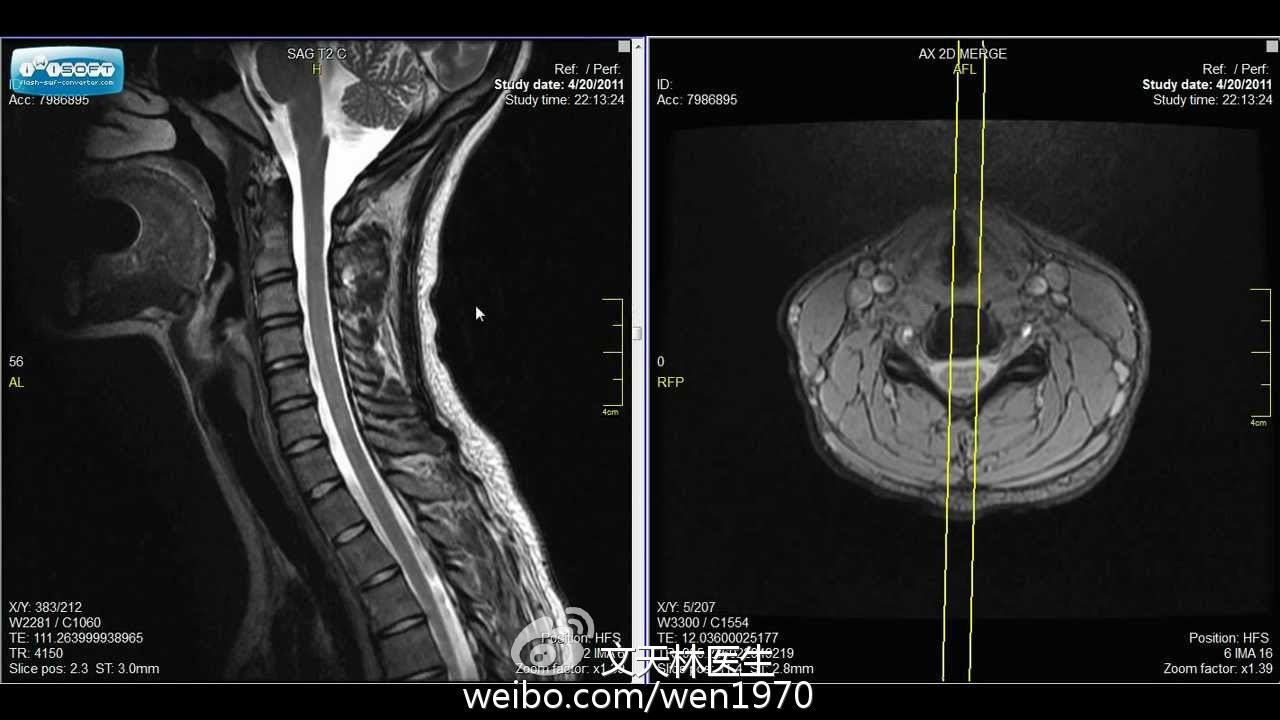

From health.wenwo.com

青年人颈肩痛,警惕颈椎病(症状诊断篇)_文天林_副主任医师_爱问健康 Can Ms Be Seen On Neck Mri mri pictures of your brain and spinal cord can help you have a fuller understanding of how ms affects you. The most important scans are t1 scans with contrast. Ms lesions can appear in. magnetic resonance imaging (mri) plays a crucial role in multiple sclerosis (ms) diagnosis, disease monitoring,. ms activity appears on an mri scan as. Can Ms Be Seen On Neck Mri.